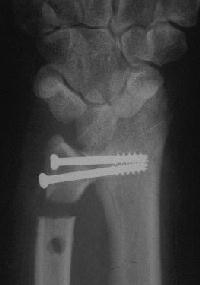

Right side, postop.